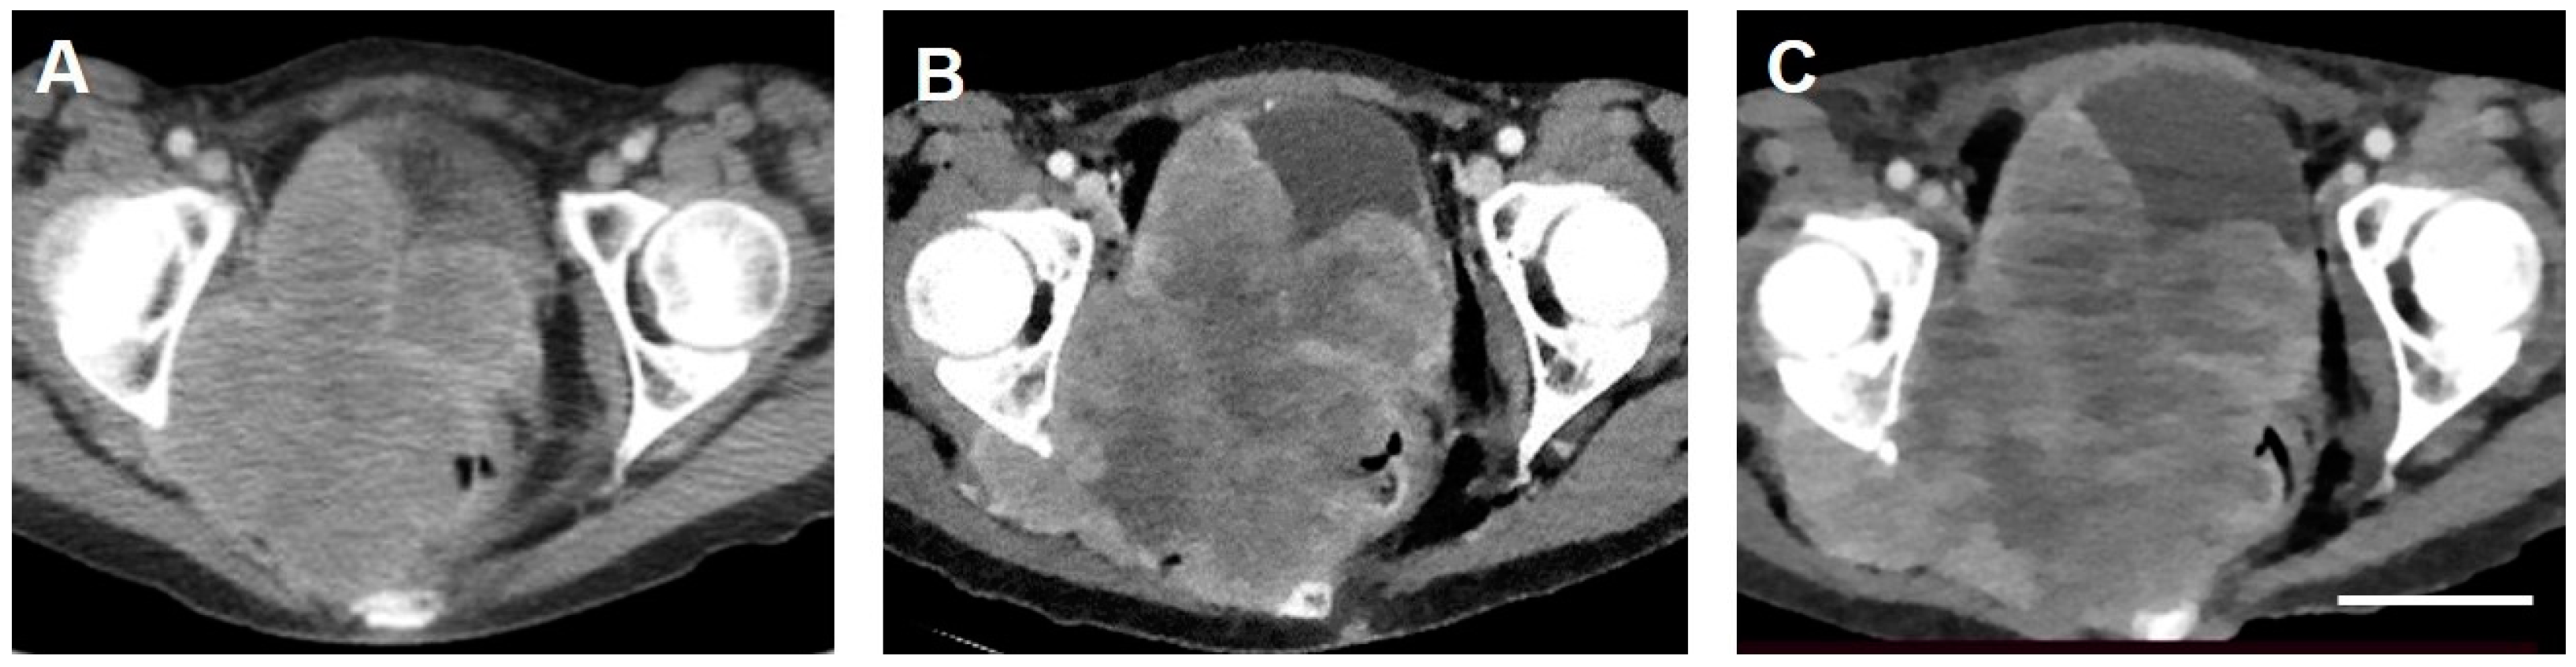

2. Case Report

2.2. Preparation, Emergency Treatment and Response